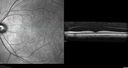

63 year old female She noticed a new thumbprint on her right eye with decreased vision March 10, 2019.  She waited a few days.  She was an eye institute where they said it was a cataract and scheduled for surgery.  She asked why if the cataracts are the same there was trouble with the one eye. He agreed and sent her to his retina specialist who noticed a problem and suggested a referral out. She has no health problems otherwise but has not been to a doctor lately.   VA OD: Dcc20/125 PHNI Ncc20/400 VA OS: Dcc20/50 PH20/32 NccJ5 IOP: TP: OD:23 OS:22 Time:15:56

Lung Cancer Metastasis to Right Eye372 views63 year old female with vision loss for 6 weeks. She had been scheduled for cataract surgery and then a tumor was found. She was ultimately diagnosed with lung cancer. Vision is 20/10000000

lung-jetop-082019.png

Metastatic Non Small Cell Lung Cancer to Choroid - Before External radiation535 views00000